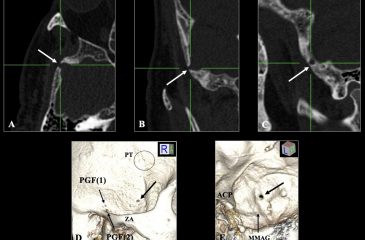

An unusual emissary foramen of the temporal bone

Highlight รายงานนี้นำเสนอรูเปิดปล่อยเลือดที่ผิดปกติในกระดูกขมับของผู้ป่วยชายอายุ 64 ปี ซึ่งไม่ตรงกับรูเปิดที่อธิบายไว้ก่อนหน้านี้ การรู้จักรูปแบบความแปรผันเช่นนี้สำคัญเพื่อลดการตีความผิดพลาดในภาพถ่ายและป้องกันภาวะแทรกซ้อนในการผ่าตัดฐานกะโหลกศีรษะ ที่มาและความสำคัญ รูเปิดปล่อยเลือด (emissary foramen) เป็นช่องขนาดเล็กในกระดูกกะโหลกศีรษะที่เชื่อมต่อระบบหลอดเลือดดำภายในกะโหลกกับเครือข่ายหลอดเลือดดำภายนอก ทั้งนี้รูเปิดปล่อยเลือดที่พบบ่อยได้รับการอธิบายอย่างดีแล้ว แต่ความแปรผันที่ผิดปกติยังไม่ได้รับความสนใจเพียงพอ การศึกษานี้รายงานกรณีรูเปิดปล่อยเลือดที่ไม่ปกติในกระดูกข้างขมับของผู้ป่วยชายอายุ 64 ปีจากภาพถ่ายเอกซเรย์คอมพิวเตอร์ความละเอียดสูง พบช่องเปิดขนาด 3.15 มม. ที่แยกออกจากโพสท์เกลนอยด์ฟอราเมนและไม่พบในฝั่งตรงข้าม โดยตำแหน่งของรูเปิดนี้มีแนวโน้มแสดงการเชื่อมต่อหลอดเลือดดำจากพีทีรอยด์เวนัสเพล็กซัสสู่ช่องหลอดเลือดดำภายในกะโหลก การรับรู้รูเปิดที่ผิดปกติประเภทนี้มีความสำคัญต่อการตีความภาพทางการแพทย์ ป้องกันการวินิจฉัยผิดพลาด และเตรียมการผ่าตัดฐานกะโหลกศีรษะอย่างรอบคอบเพื่อหลีกเลี่ยงภาวะแทรกซ้อนเช่นเลือดออกโดยไม่คาดคิด Abstract The sternalis muscle, a well-documented […]